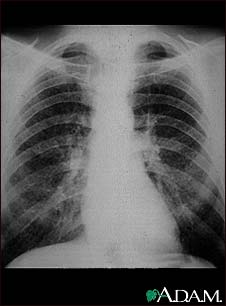

Coal worker's lungs - chest X-ray

This chest x-ray shows coal worker's lungs. There are diffuse, small, light areas on both sides (1 to 3 mm) in all parts of the lungs. Diseases that may result in an x-ray like this include: simple coal workers pneumoconiosis (CWP) - stage I, simple silicosis, miliary tuberculosis, histiocytosis X (eosinophilic granuloma), and other diffuse infiltrate pulmonary diseases.